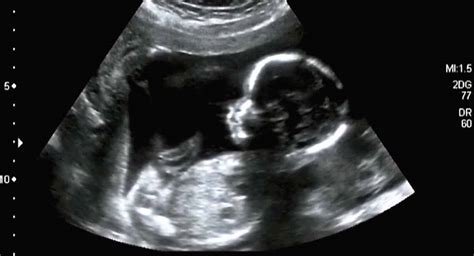

De 20-wekenecho: een gedetailleerd onderzoek

De 20-wekenecho, ook wel het structureel echoscopisch onderzoek (SEO) genoemd, is een uitgebreide echo die doorgaans tussen week 18 en 22 wordt uitgevoerd. Een ervaren echoscopist gebruikt geavanceerde apparatuur om systematisch alle organen en structuren van je baby te bekijken.

- Hersenen: Er wordt gekeken naar normale structuren en vloeistofruimtes.

- Hart: De vier kamers, de bloedstroom en de algemene structuur worden beoordeeld.

- Nieren: Grootte en functie worden geëvalueerd.

- Blaas: De aanwezigheid en vulling worden gecontroleerd.

- Maag: De aanwezigheid van de maag wordt vastgesteld.

- Wervelkolom: De sluiting van de wervelkolom wordt geïnspecteerd.

- Buikwand: De intactheid van de buikwand wordt gecontroleerd.

- Ledematen: De lengte en het aantal vingertjes en teentjes worden beoordeeld.

- Vruchtwater: De hoeveelheid vruchtwater wordt beoordeeld; te veel of te weinig kan een signaal zijn.

- Placenta: De positie van de placenta wordt vastgesteld. Een laag gelegen placenta wordt gevolgd met herhalingsecho's.

Voor de overgrote meerderheid van de echo's ziet alles er goed uit, wat leidt tot een opgelucht en blij gevoel. In een klein percentage van de gevallen kan een afwijking worden gevonden die nader onderzoek vereist, of kan een deel van de echo niet goed worden beoordeeld, waarvoor een herhalingsecho wordt gepland. Het is belangrijk om je niet te veel zorgen te maken voor de echo.